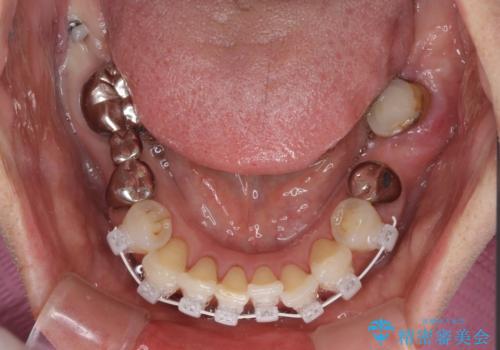

- 前歯の歯肉の腫れを気にして来院された患者様です。

前歯のみならず、奥歯の銀歯や下顎前歯のデコボコなど、色々と気になる部分を治したいとのことでした。

前歯は抜歯が必要であったので、抜歯を行い、その後歯肉移植をおこなった上でオールセラミックブリッジによる補綴治療を行うこととしました。

下顎と上顎臼歯部については矯正治療を行い、奥歯の欠損部位はオールセラミックブリッジを、その他の銀歯はセラミックインレーなどにより治療を行うこととしました。